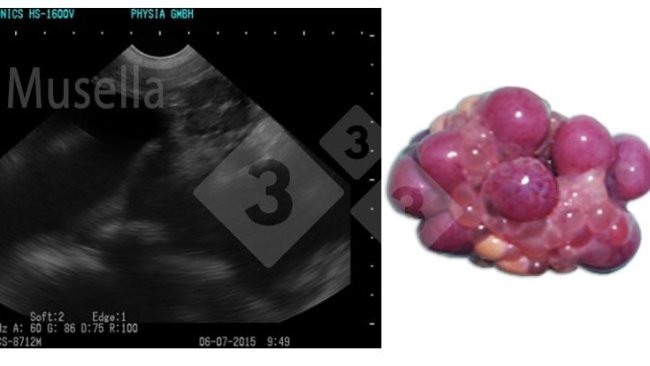

L'échographie peut être utilisée pour visualiser les structures ovariennes, évaluer l'état pubertaire et diagnostiquer les pathologies ovariennes.